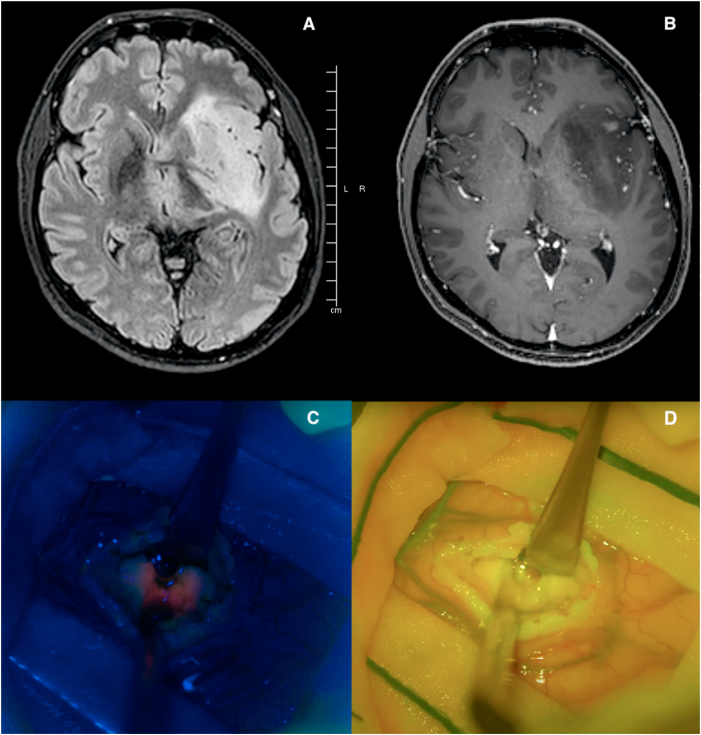

Objective: Fluorescence-guided surgery (FGS) has been increasingly used to support glioma surgery to obtain a maximal extent of resection (EOR). Current evidence in lower-grade gliomas does not support the routine use of FGS obtained with the most common fluorescence agents (e.g. 5-ALA and fluorescein sodium). However, the combination of these two dyes has not been extensively explored yet. Main objective of this study is to evaluate the role of 5-ALA and FS in LGGs surgery for tumor detection, margin definition, and prognostic relevance.

Methods: 112 patients affected by a histologically confirmed adult-type diffuse glioma grade 2-3 molecularly defined underwent craniotomy in "Città della Salute e della Scienza" hospital (Turin, Italy). Surgery has been performed under general anesthesia with the previous administration of both 5-ALA (20 mg/kg) and fluorescein sodium (3 mg/kg). We retrospectively investigated clinical, radiological, histological and molecular data. Fluorescence positive rate and pattern have been reported both for 5-ALA and for fluoresceine.

Results: We included 69 patients with astrocytoma IDH-mutant and 43 with oligodendroglioma IDH-mutant 1p19q-codeleted. Seventeen cases were positive for both 5-ALA and FS (15.1 %), 24 for 5-ALA (21.4 %) only, 1 for FS (1.0 %) only, 70 were negative (62.5 %). The relationship between intraoperative fluorescence and the presence of foci with contrast enhancement uptake on the preoperative MRI was statistically significant (p < 0.001) for both the dyes. 5-ALA intraoperative detection had a statistically significant impact on the overall survival (OS) (HR: 2.51, 95 % CI: 1.25-5.01, p = 0.009) and progression-free survival (PFS) (HR: 2.46, 95 % CI: 1.34-4.52, p = 0.004). Additionally, both FS and 5-ALA fluorescence slightly prevailed in grade 3 gliomas, especially 5-ALA.

Conclusion: The results achieved in this study do not support the role of 5-ALA and FS to intraoperatively define the extent of resection, because of low fluorescence rates. Nevertheless, 5-ALA expression could be used to intraoperatively identify more aggressive foci and add useful prognostic information before the histological analysis. Indeed, FS is mostly related to blood-brain barrier damage and, thus, with contrast enhancement in MRI.